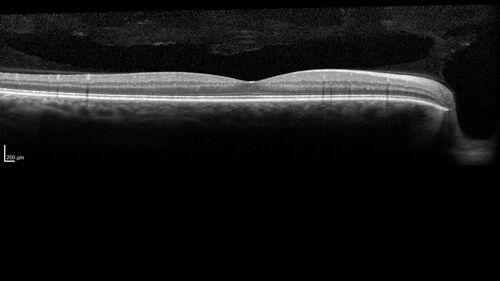

Class 2 choroidal melanoma

48 year old man with no visual complaints referred by optometrist.

Brachytherapy was done and biopsy showed a class 2 melanoma. 2 years later the patient developed liver metastases.